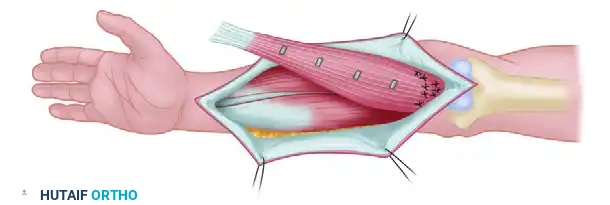

Judet and Patel Subperiosteal Decortication

For recalcitrant cases, Judet and Patel described an elegant biological technique: subperiosteal decortication. This involves elevating osteoperiosteal flaps (bone chips attached to the periosteum) around the nonunion site, followed by rigid internal fixation (plates or IM nails) with compression. In their series of 195 femoral nonunions, union failed in only 4.6% of cases.

Figure 59-24: Judet and Patel subperiosteal decortication. (A) Exposure of the femur, demonstrating autogenous bone chips elevated subperiosteally. (B) Cross-section illustrating the separation of cortical bone and periosteum from the femoral shaft.